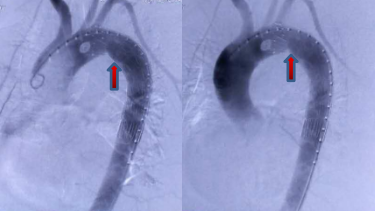

术中主动脉造影:主动脉弓小弯侧主动脉壁向外膨出

术后主动脉造影:主动脉支架植入后瘤体消失